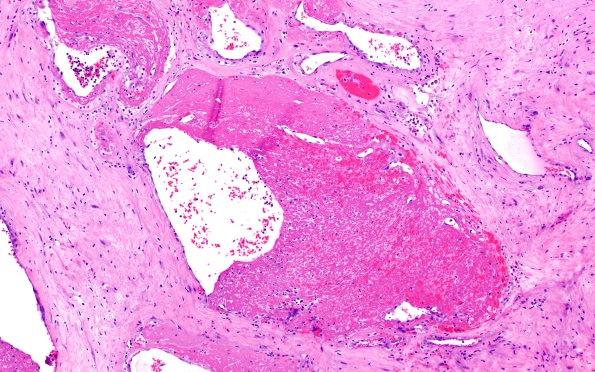

32B6 Schwannoma (Case 32) H&E 10X 2

This image shows fibrin deposition associated with tumor vasculature. (H&E)